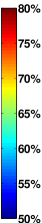

Finally, in order to convey the regional distribution of the edges recovered by fused Lasso, we rendered implicated edges on canonical -D brains (Fig. 10; these figures were generated with the BrainNet Viewer, http://www.nitrc.org/projects/bnv/). We focus on the three sets of network-to-network connections, intra-frontoparietal, frontoparietal-default, and intra-cerebellum, as these three networks have particularly extensive evidence of their involvement in schizophrenia (see Discussion in Sec. 4). It is noteworthy that lateral prefrontal cortex, an important region in frontoparietal network, is well represented in the fused Lasso map. Edges involving this region represent of the intra-frontoparietal connections and of the frontoparietal-default network connections. This finding is consistent with previous studies of schizophrenia that emphasize the importance of this region (see Discussion in Sec. 4).

(node color)

(edge color)

Intra-Frontoparietal (6-6)

Frontoparietal-Default (6-7)

Intra-Cerebellum (12-12)

Finally, additional evidence that fused Lasso recovered more interpretable discriminative features for the schizophrenia dataset comes from comparing visualizations of the respective weight vectors from the three regularizers (see Fig. 9). The map of the fused Lasso support shows more prominent and clearly localized alterations in connectivity involving frontoparietal network, default network, and cerebellum, among other regions. These networks also exhibited increased node degree, indicating diffuse connectivity alterations with other networks. Interestingly, these networks are among the most commonly implicated in schizophrenia. Frontoparietal network, which has multiple important hubs in prefrontal cortex, is involved in executive processing and cognitive control [80], and has been shown to exhibit abnormal activation (see [81] for a quantitative meta-analysis) and connectivity ([82]; [79]; see [68] for a review) in schizophrenia. Fused Lasso also recovered altered connectivity between frontoparietal network and default mode network, an important brain network involved in autobiographical memory and internally generated mental simulations [83, 84]. The weight vectors shown in Fig. 9 and the -D brains shown in Fig. 10 evidence a substantial number of aberrant connections between frontoparietal network and default network, with a predominance of reduced connectivity in schizophrenia. Frontoparietal network and default network become more interconnected throughout childhood and adolescence [85, 86], which might reflect development of top-down cognitive control by frontoparietal regions over default network. Reduced connectivity between these two networks is among the most commonly observed findings in connectivity research in schizophrenia [87, 82, 88, 89, 90], and has been proposed to reflect disruptions and/or delays in normal trajectories of maturation [82]. It is also noteworthy that a sizable portion of the aberrant connection within frontoparietal cortex and between frontoparietal network and default network involved dorsal lateral prefrontal cortex (see results in Sec. 3.2). This region is perhaps the most frequently described as being abnormal in schizophrenia [91, 92, 89]. A third network highlighted by fused Lasso is cerebellum, which is featured in the influential ‘cognitive dysmetria’ hypothesis of schizophrenia [93]. Abnormalities in cerebellum have been found in post-mortem [94], structural [95], and functional connectivity studies [96].